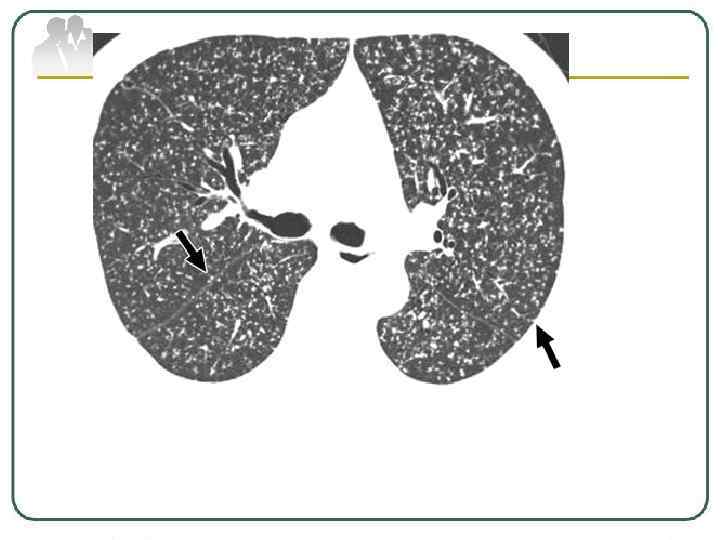

Очаговый туберкулез легких характеризуется наличием немногочисленных очагов, преимущественно продуктивного характера, локализующихся в ограниченном участке одного или обоих легких и занимающих 1 - 2 сегмента, и малосимптомным клиническим течением. К очаговым формам относятся как недавно возникшие, свежие ("мягко-очаговые") процессы с размером очагов менее 10 мм, так и более давние (фиброзно-очаговые) образования с явно выраженными признаками активности процесса.